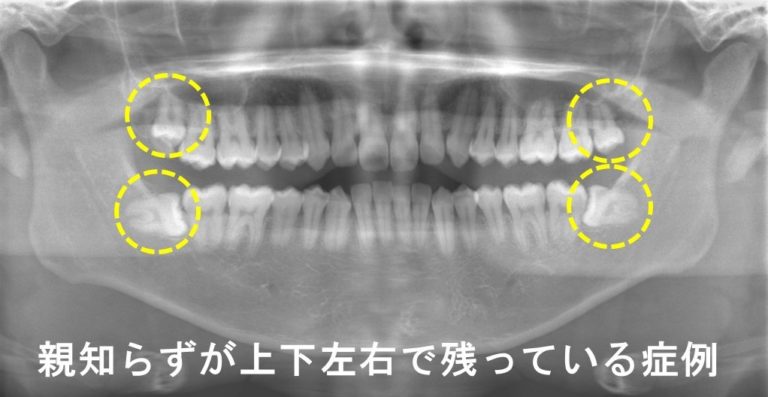

日本人の親知らずは大概が横を向いて埋まっていたり、半分だけ頭を出して歯肉に埋まっていたり、あらぬの方向を向いてはえていたりと、欧米人と比べて骨格的な理由もあり、きちんとはえてくることは少ないです。

こういった症状のある親知らずを残しておいておくことのリスクには

①親知らず自体が虫歯で痛くなってしまう

②隣の歯が虫歯になってしまう

③隣の歯が歯周病になってしまう

④炎症が広がって顔面まで腫れてきてしまう

などのいろいろな可能性がありますが、②③のように隣の歯に悪影響を及ぼしてしまうことが一番心配です。